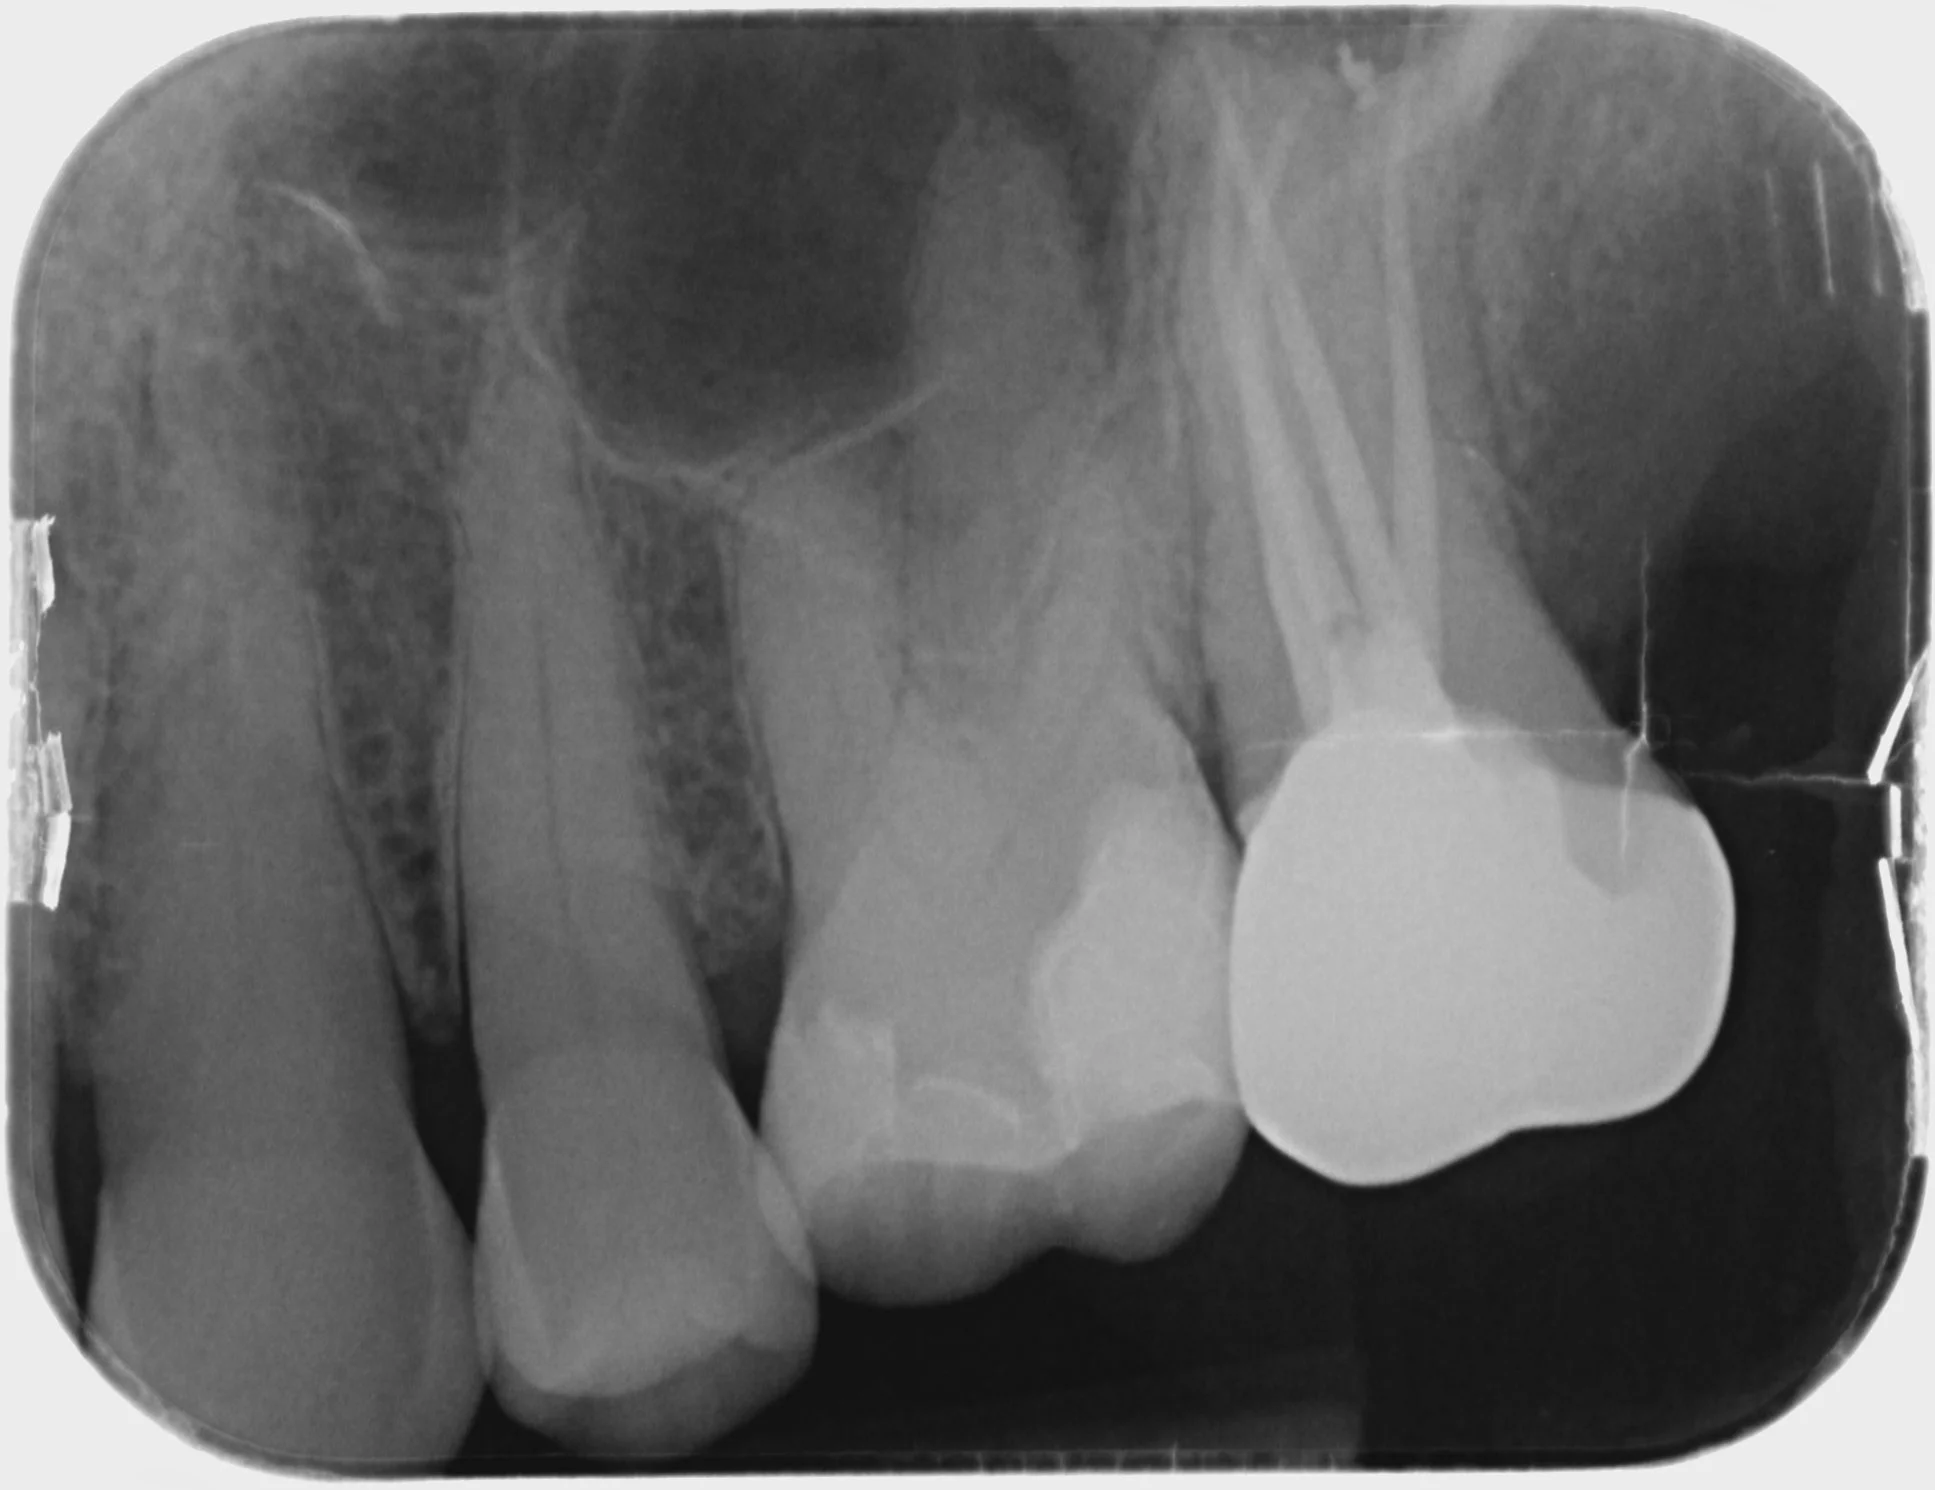

Endodontics